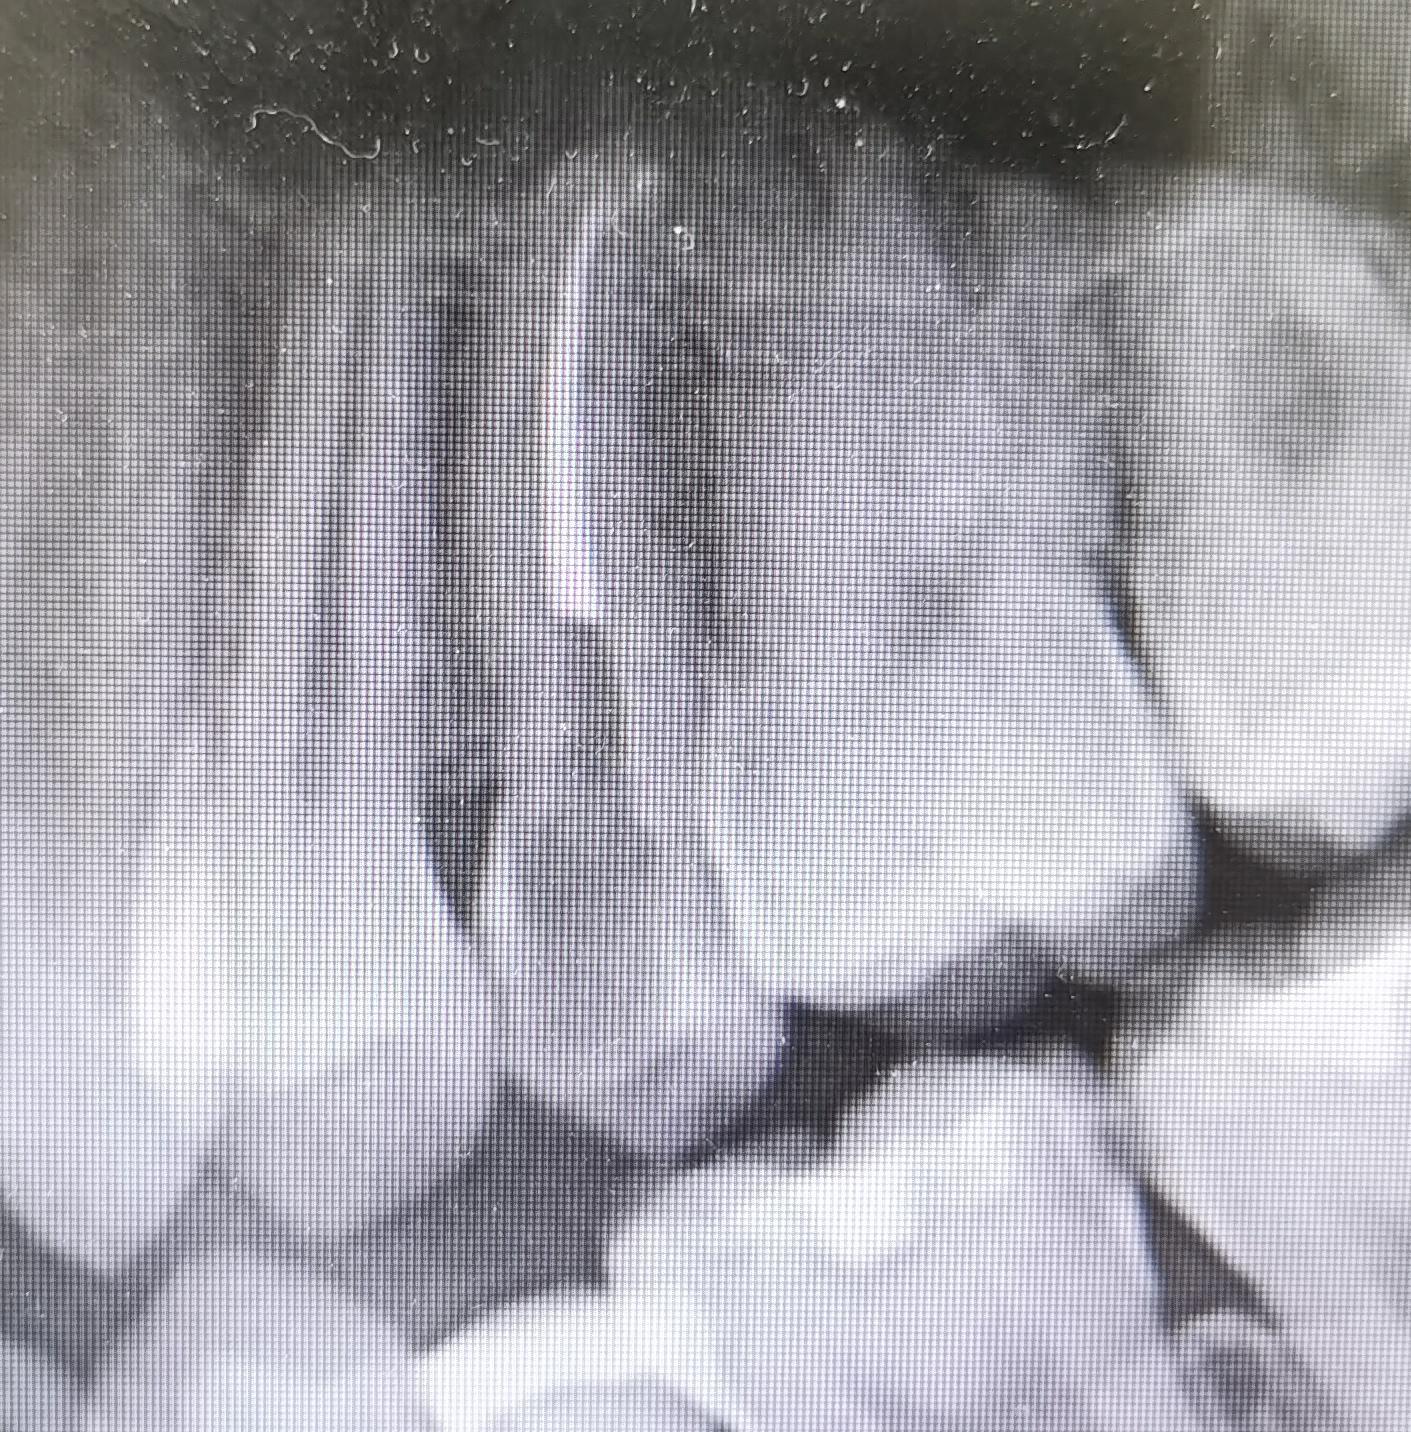

经过系统的口腔检查,我发现患者25牙近中远中邻颌面有深大龋坏,腐质多,检查过程中患者出现痛感,停止操作后,持续疼痛一分钟左右,牙龈缘轻度红肿,对冷刺激敏感。同时X线提示:25牙冠龋坏已经到达髓腔(牙神经)。由于患者对冷刺激敏感,影像学发现牙神经受到炎症波及,有深大龋洞,符合牙髓炎表现,遂诊断为“25牙髓炎”。

因为根管治疗需要利用牙科手机及车针暴露牙髓,继而去除牙齿的龋坏,这个过程可能使牙神经受激,引起较剧烈的疼痛。为了减轻患者疼痛,操作前给予甲哌卡因局部浸润麻醉,然后在根管下打开牙齿髓腔去除龋坏,并完成拔髓,最后给予iRoot sp+热牙胶加压充填,复拍X片恰填后,使用光固化玻璃离子充填,使牙齿冠部暂时封存。并告诉患者1-2周后复诊,进行最后一次桩冠修复。

术前患者25牙近远中及咬合面存在深大龋坏,术后患者腐坏牙体组织去除干净,牙髓炎症感染控制,根管及冠部填充完美,咬合没有出现不适症状,疼痛消失,嘱其避免喝碳酸饮料,少吃甜食,多吃富含维生的的绿色蔬菜,用巴氏刷牙法刷牙,定期来到口腔科复查,随后予以离院。